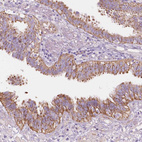

Immunohistochemical staining of human hippocampus shows moderate cytoplasmic positivity in neurons.